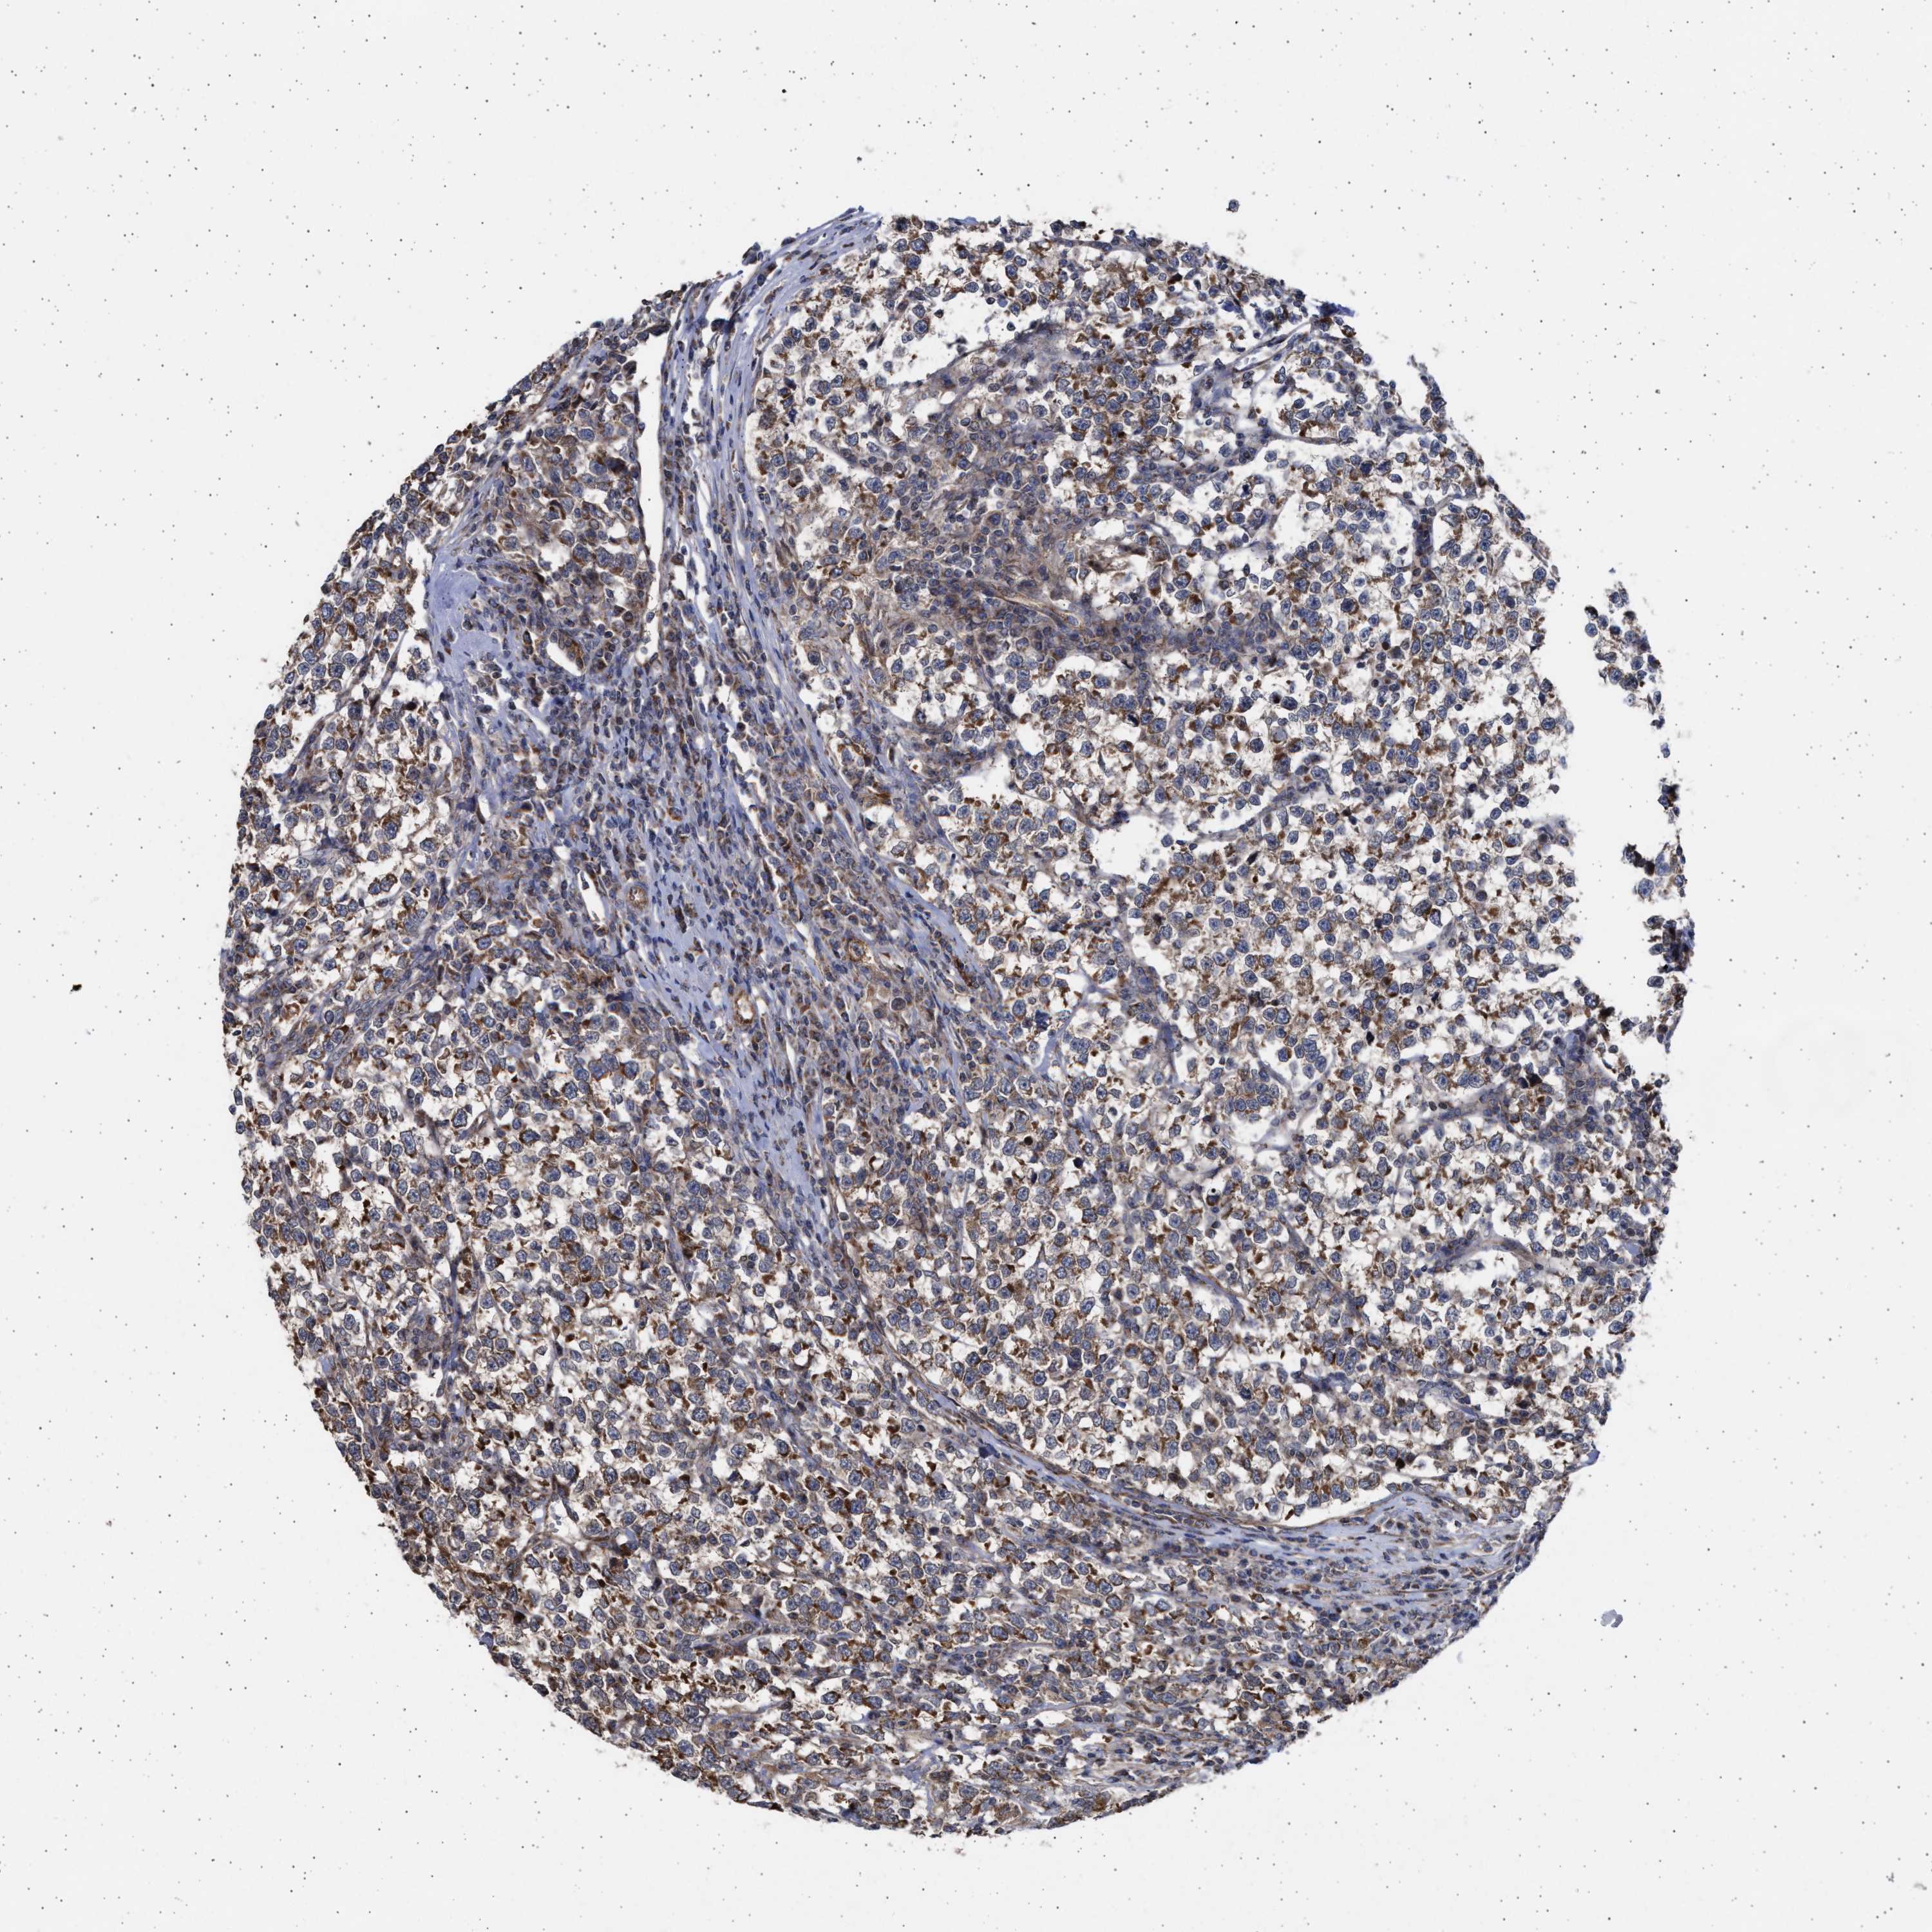

TESTIS CANCER - Protein expressioni

A mouse-over function shows sample information and annotation data. Click on an image to view it in a full screen mode. Samples can be filtered based on level of antibody staining by selecting one or several of the following categories: high, medium, low and not detected. The assay and annotation is described here.

Note that samples used for immunohistochemistry by the Human Protein Atlas do not correspond to samples in the TCGA dataset.

Antibody stainingi

Antibody staining in the annotated cell types in the current human tissue is reported as not detected, low, medium, or high, based on conventional immunohistochemistry profiling in selected tissues. This score is based on the combination of the staining intensity and fraction of stained cells.

Each image is clickable and will lead to virtual microscopy that enables deeper exploration of all samples and also displays staining intensity scores, fraction scores and subcellular localization as well as patient and tissue information for each sample.

Antibody HPA023010

Antibody HPA052380

Carcinoma, Embryonal, NOS

Seminoma, NOS

Teratoma, malignant, NOS